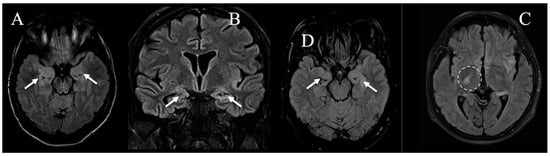

| Major MRI findings | Left parieto-occipital and thalamic FLAIR hyperintensities, with bilateral mesial temporal changes | Left mesial temporal lobe cortical thickening with FLAIR hyperintensity (subtle changes in right internal capsule) | Posterior left mesial temporal lobe FLAIR hyperintensity and ribbon-like cortical thickening | Right cortical frontal precentral FLAIR hyperintensity with no cortical thickening; subtle bilateral temporal changes (left > right) | Left cortical frontal-parietal, precentral FLAIR hyperintensity with ribbon-like thickening; subtle bilateral temporal changes (left > right) |

| Symmetry | Asymmetric; main alteration unilateral | Asymmetric; main alteration unilateral | Asymmetric; main alteration unilateral | Asymmetric; main alteration unilateral | Asymmetric; main alteration unilateral |

| Localization | Extra-limbic | Limbic system | Limbic system | Extra-limbic | Extra-limbic |